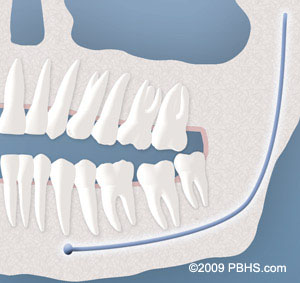

Third molars are commonly referred to as wisdom teeth. They are usually the last teeth to develop and are located in the back of your mouth, behind your second molars. Their development is usually completed between the middle teenage years and early twenties, a time traditionally associated with the onset of maturity and the attainment of wisdom.

Although most people develop and grow 32 permanent adult teeth, many times their jaws are too small to accommodate the four wisdom teeth. When inadequate space prevents the teeth from erupting they are called impacted. This indicates their inability to erupt into the proper position for chewing and cleaning.

diagramof x ray and impacted wisdom teeth 1

We will need to see you for a consultation to determine if you will benefit from wisdom tooth removal. A special x-ray of your mouth and jaws (panorex) will be taken to determine if your wisdom teeth are impacted, if there is room for them to erupt, and how difficult it will be to have them removed.